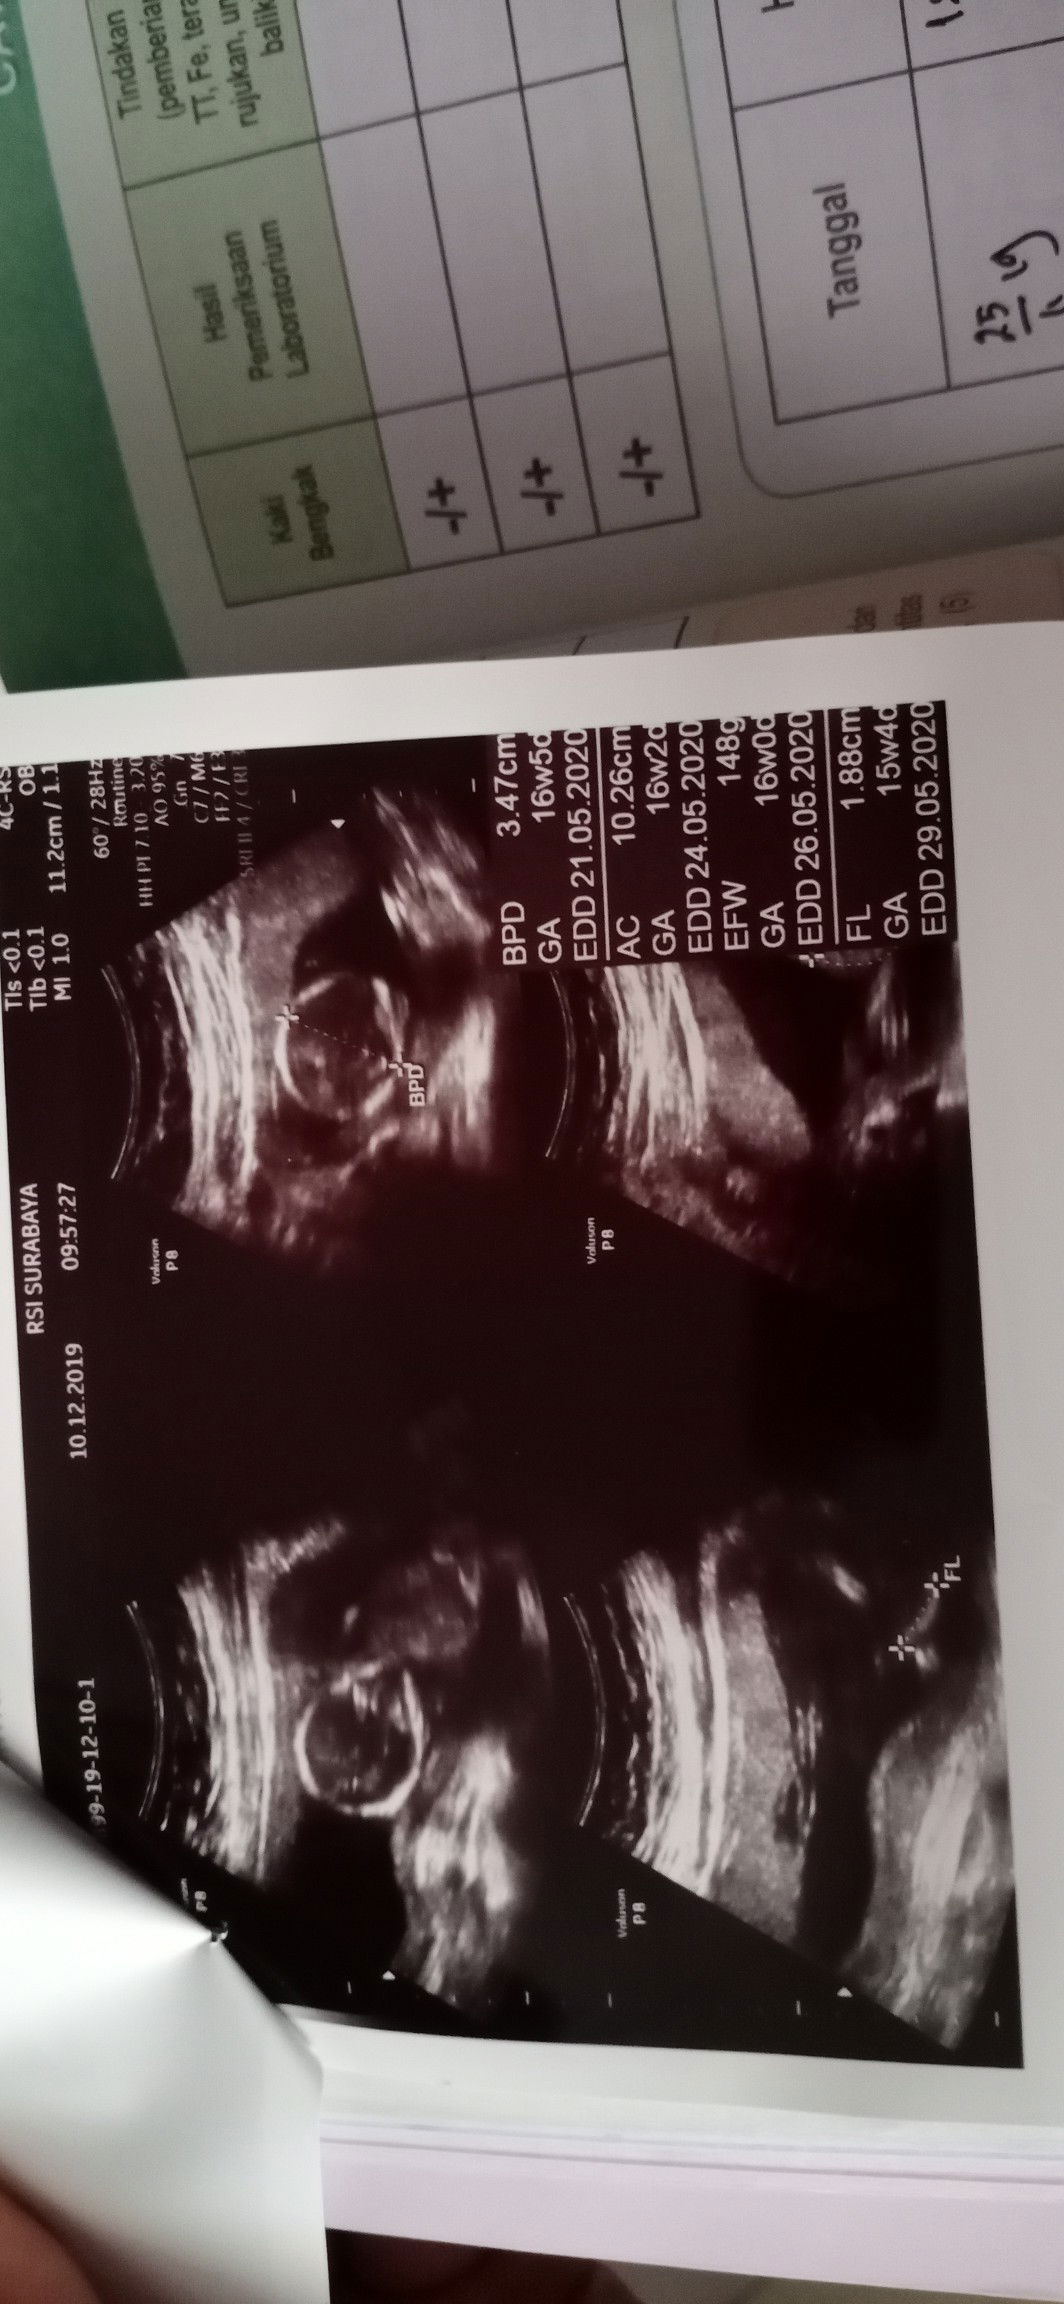

Penantian 2.5 Tahun

Alhamdulillah barakallah Allah memberikan kejutan yang tak terduga* ??